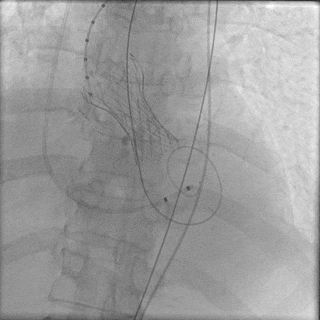

瓣膜稳步脱钩后,造影显示瓣膜位置合适,冠脉灌注良好,无瓣周漏。

稳步脱钩

最终造影

手术即刻超声测量,主动脉瓣工作良好,无反流,与术前超声测量数据对比,流速、跨瓣压差得到有效改善。

超声评估

术前、术后血流动力学评估